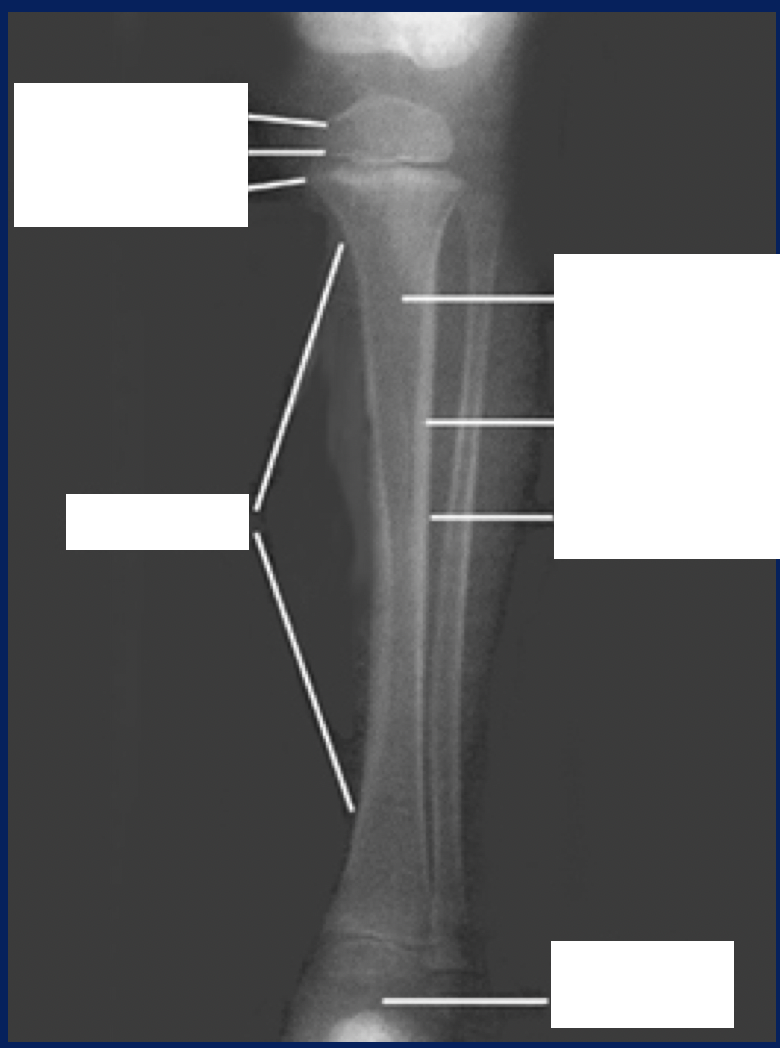

Bones increase in length by […] growth of epiphyseal plate (area of cartilage)

Interstitial

Bones increase in width by […] growth (osteoblasts lay down matrix in layers parallel to the outer surface)

Appositional